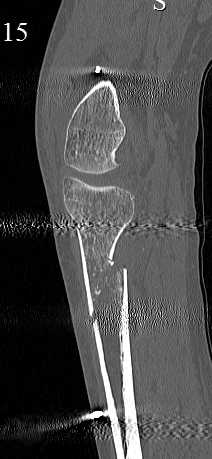

[Ortho] перелом проксимальной тибии + вывих бедра

Серия КТ сканов в аппарате